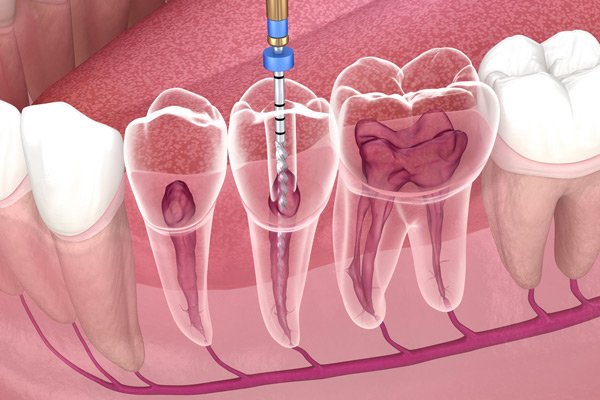

Há também doenças que afetam a polpa dental (nervo do dente), tecido em torno das raízes e a especialidade que trata essa parte é a endodontia ou o tratamento de canal.

Após o diagnóstico conclusivo e confirmada a necessidade de realizar o canal, o profissional remove toda a polpa do dente infectada, na sequência é feita a limpeza e desinfecção dos canais radiculares que são esvaziados e devidamente higienizados, após essa etapa é feito o preenchimento dos canais e por fim a restauração do dente com resina ou coroa.